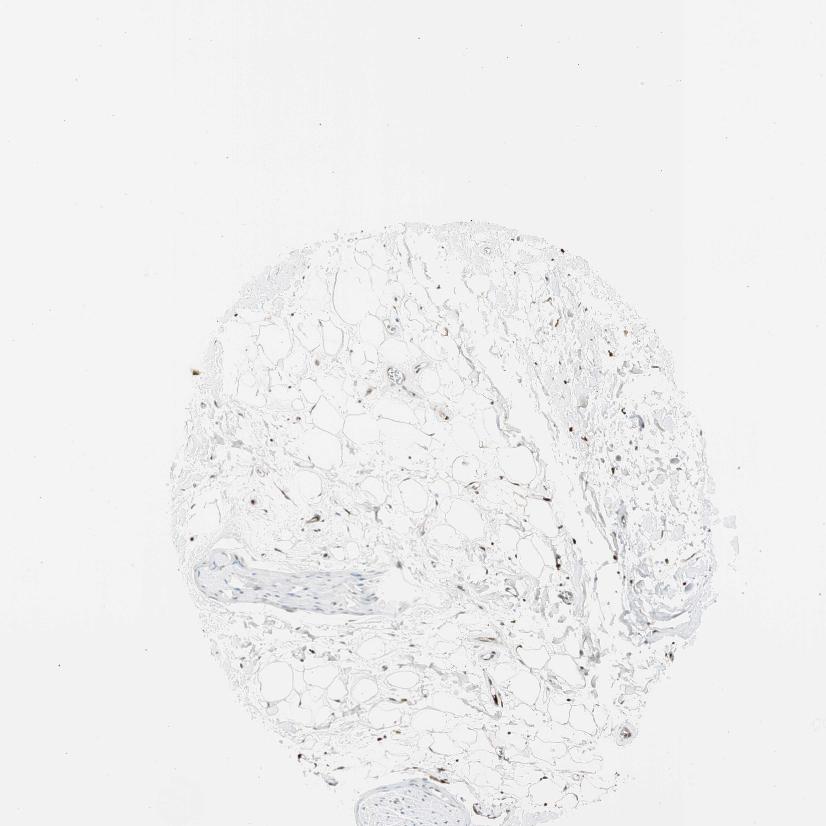

SOFT TISSUE 2 - Antibody stainingi

Antibody staining in the annotated cell types in the current human tissue is reported as not detected, low, medium, or high, based on conventional immunohistochemistry profiling in selected tissues. This score is based on the combination of the staining intensity and fraction of stained cells.

Each image is clickable and will lead to virtual microscopy that enables deeper exploration of all samples and also displays staining intensity scores, fraction scores and subcellular localization as well as patient and tissue information for each sample.

Antibody HPA017017Antibody CAB015221

Fibroblasts Not detectedMedium

Peripheral nerve Not detected-